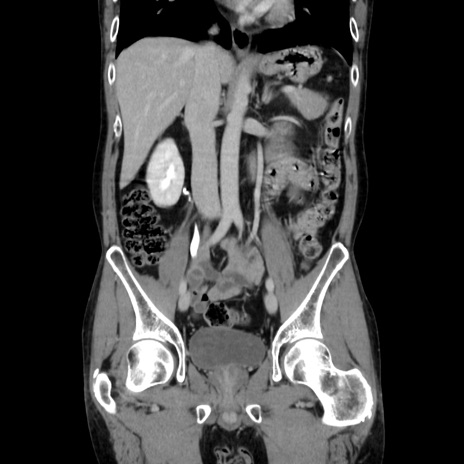

症例37(冠状断像)

【症例】40歳代 男性

【主訴】腹痛

【現病歴】4時間ほど前に電車に乗車中に臍部上より腹痛出現。徐々に増悪し起立困難となり、救急外来受診。生ものは数日食べていない。今朝お雑煮を食べた。

【身体所見】BT 36.8℃、BP 117/84mmHg、HR 91/min、SpO2 97%、苦悶様、腹部:臍上部広範囲圧痛あり、反跳痛±

【データ】WBC 8100、CRP 0.03